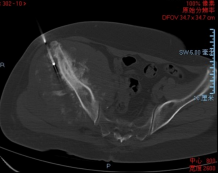

术前影像

穿刺活检提示骨盆软骨肉瘤

日前,安医大一附院骨病骨肿瘤外科胡勇教授团队成功完成一例复杂骨盆Ⅰ+Ⅱ+Ⅲ+Ⅳ区肿瘤切除与3D打印组配式半骨盆假体重建手术。患者为女性,53岁,下腰痛半年余,右侧臀部膨隆,右侧下肢轻度浮肿。右侧髂棘髂窝及臀部可触及巨大肿物,压痛明显,右髋外展前屈活动受限,右侧大腿感觉麻木,右足感觉运动正常。骨盆肿瘤切除重建是骨科专业中难度极大、风险极高的手术。骨盆肿瘤约占原发骨肿瘤的3%~4%,其中以软骨系统肿瘤最为多见,其次为骨巨细胞瘤、成骨肉瘤等,儿童尤文肉瘤亦好发于骨盆。

骨盆恶性肿瘤常潜在发展,由于骨盆位置较深,肿瘤早期很难发现,从第一次出现症状到诊断明确有时需要很长时间,当出现临床症状时,肿瘤体积已较大,因而手术切除相当困难。骨盆肿瘤血供丰富,手术出血多、难度大。另外,骨盆形态特殊,解剖复杂,切除肿瘤的同时,需要重建骨盆结构和肢体功能,技术要求高。